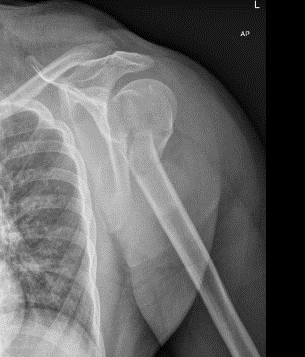

U bent onder behandeling bij Amsterdam UMC omdat u uw schouderkop heeft gebroken. Afhankelijk van het soort breuk, heeft uw traumachirurg in overleg met u besloten de breuk zonder operatie te behandelen. In deze folder krijgt u informatie over de behandeling en het herstel na een gebroken kop van de bovenarm zonder operatie.Per fase van het herstel leggen we uit welke adviezen u kunt opvolgen en welke oefeningen u kunt doen. Voor het genezingsproces is het belangrijk dat u deze instructies stap voor stap opvolgt.